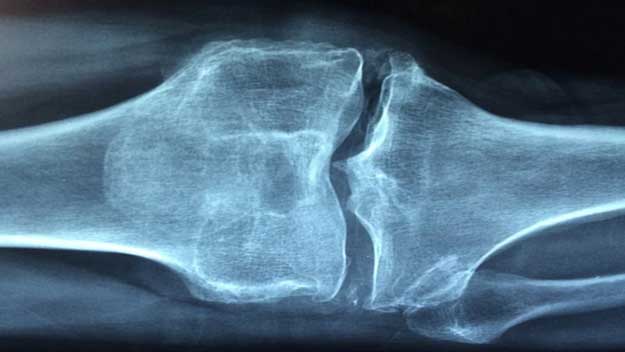

Denzitometrie neboli měření hustoty minerálů v kostech je jedním z nejúčinnějších způsobů prevence osteoporózy. Ta může v pokročilém stádiu způsobovat ošklivé zlomeniny dokonce i při lehkém nárazu nebo kýchnutí. Nemoc postihuje takřka každou třetí ženu po menopauze, nevyhýbá se ale ani mužům.

Ačkoliv osteoporóza sama o sobě nebolí, její symptomy mohou být velmi nepříjemné. Jedná se především o časté zlomeniny, které mohou v pokročilých stádiích vznikat i jen v důsledku rychlejšího pohybu, kašle či kýchnutí. Osteoporóza, tedy nemoc řídnutí kostí, přichází nejčastěji s věkem. Trpí jí až třetina žen po menopauze, ve věku nad 50 let ale postihuje i 15-30 % mužů.

„Denzitometrie je lokálním vyšetřením kostní tkáně. Provádí se pomocí zařízení vyzařujícího slabé rentgenové záření. Celý proces je tedy rychlý, a navíc zcela bezbolestný,“ upřesňuje MUDr. Kateřina Zezulová. Díky denzitometrii může lékař zhodnotit hustotu kostní tkáně a obsah minerálů v kostech. Na základě výsledků vyšetření pak doporučí i další postup. Obvykle se jedná o prevenci zlomenin a užívání léků na posílení kostí, případně k úpravě hladiny některých hormonů.